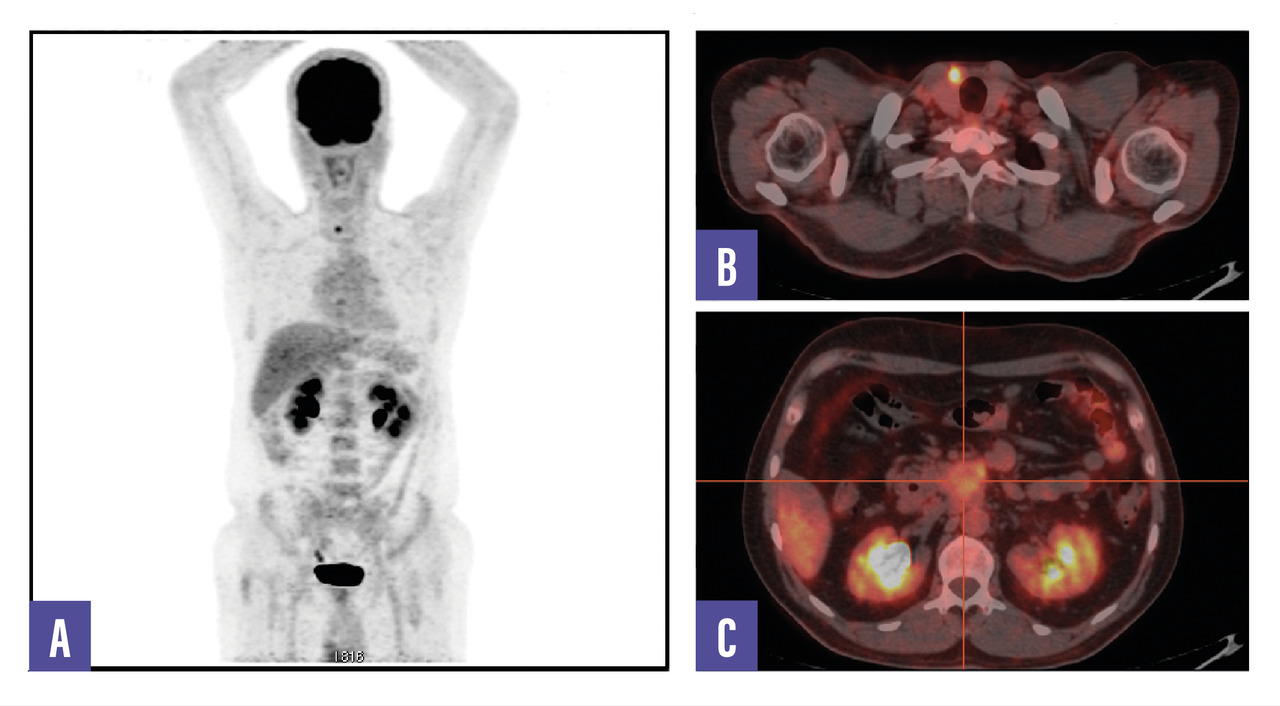

Un homme de 53 ans, sans antécédents, consulte pour des douleurs abdominales diffuses évoluant depuis plusieurs semaines. Le bilan biologique est normal. Une tomodensitométrie abdomino-pelvienne met en évidence une masse rétropéritonéale infiltrante associée à une adénopathie lombo-aortique. La tomographie par émission de positons (TEP-TDM au 18F-FDG) montre un hypermétabolisme léger de la lésion rétropéritonéale, mais l’adénopathie ne fixe pas le FDG (fig. 1). Un foyer hypermétabolique thyroïdien droit est également détecté. Une biopsie échoguidée confirme une tumeur neuro-endocrine digestive bien différenciée de grade 2 (Ki- 67 à 12 %). La scintigraphie au 99mTc-Tektrotyd révèle une fixation intense de l’adénopathie, compatible avec une pathologie neuro-endocrine exprimant les récepteurs de la somatostatine (fig. 2). Un nodule thyroïdien droit conduit à une thyroïdectomie totale, confirmant un microcarcinome papillaire.